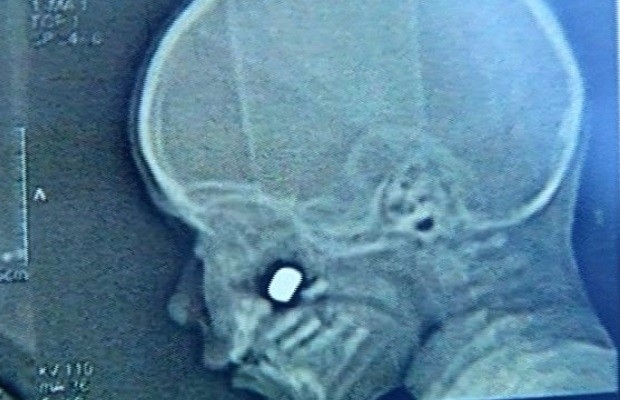

Bala retirada

A bala que atingiu o rosto do menino de 2 anos ficou alojada abaixo do olho direito. Na tarde de quinta-feira (16), a criança passou por um cirurgia para a retirada do artefato."Felizmente correu tudo bem. Conseguimos remover o projétil, que provavelmente será encaminhado para a parte de balística", relatou o médico.